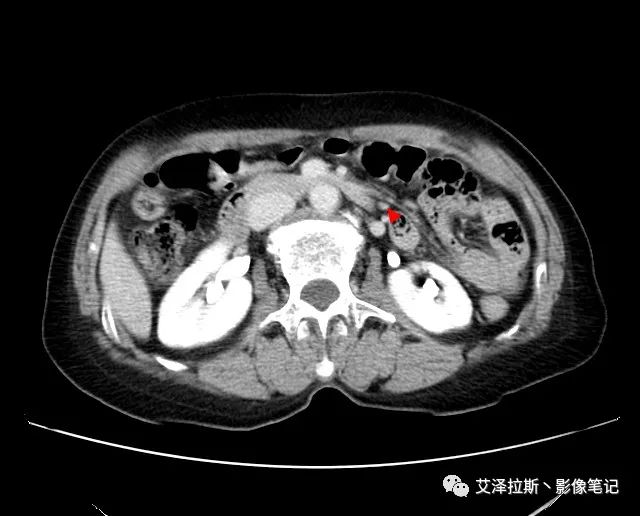

【影像所見】 胃竇部狹窄,胃壁環形增厚,小彎側見一巨大潰瘍,周圍伴“環堤征”,漿膜面不完整,胃周脂肪見網格狀條索影,病灶與肝臟左葉、胰腺鉤突脂肪間隙消失,增強掃描病灶明顯強化。引流區內約15個區域淋巴結受累。

【診斷意見】 胃竇部胃癌(T4N3期) 該病例腫塊突破漿膜層,與肝臟左葉、胰腺鉤突分界不清,脂肪界面消失,定為T4期; 受累及的淋巴結為15個區域,定為N3; 有無遠處轉移尚不明確,所以M期暫時無法確定。